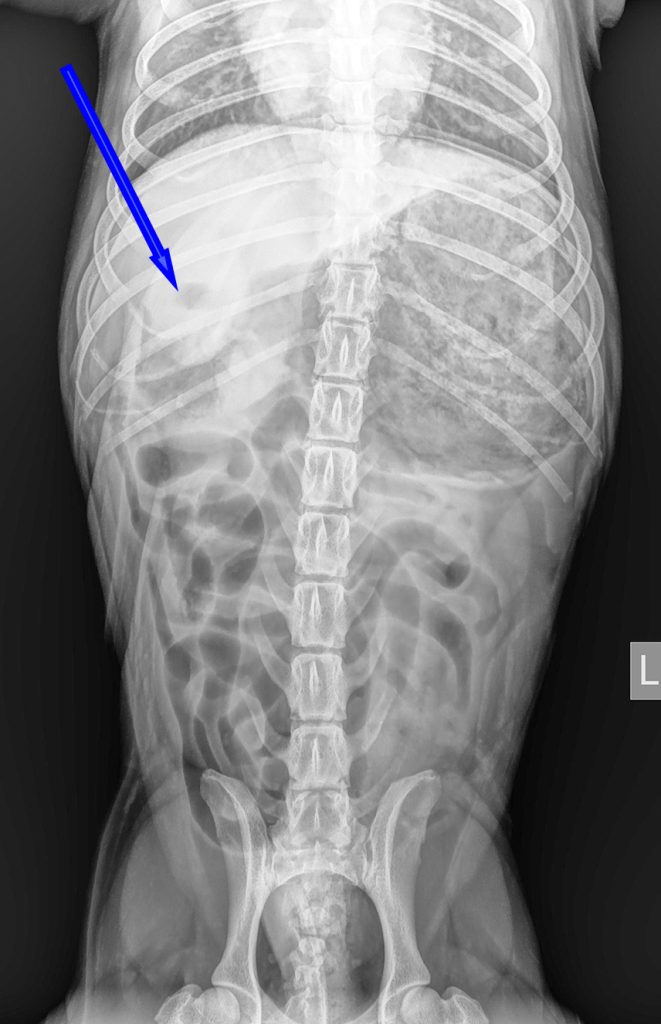

Bij het algemeen onderzoek was de buik gevoelig bij het navoelen en er leek veel gasvorming aanwezig te zijn. Op de röntgenfoto was er een grote maag met veel vulling zichtbaar, waarbij er ook een soort buisvormige structuur aanwezig leek te zijn. Het leek er dus op dat er een vreemd voorwerp in de maag zat. Aangezien Joep al meerdere keren had gebraakt zonder dat er iets uit kwam, was het advies om dit voorwerp operatief te verwijderen.